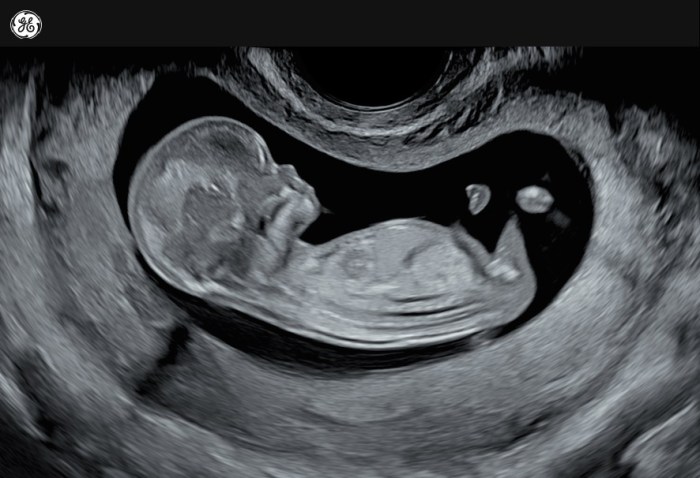

- Ultrasonografi (USG): USG trimester pertama merupakan pemeriksaan pencitraan yang menggunakan gelombang suara untuk melihat janin di dalam rahim. Pemeriksaan ini bertujuan untuk memastikan kehamilan intrauterin (kehamilan di dalam rahim), menentukan usia kehamilan, dan mendeteksi kelainan pada janin atau plasenta. Selain itu, USG juga dapat mendeteksi kehamilan kembar.

- USG: Memastikan kehamilan intrauterin, menentukan usia kehamilan, dan mendeteksi kelainan.